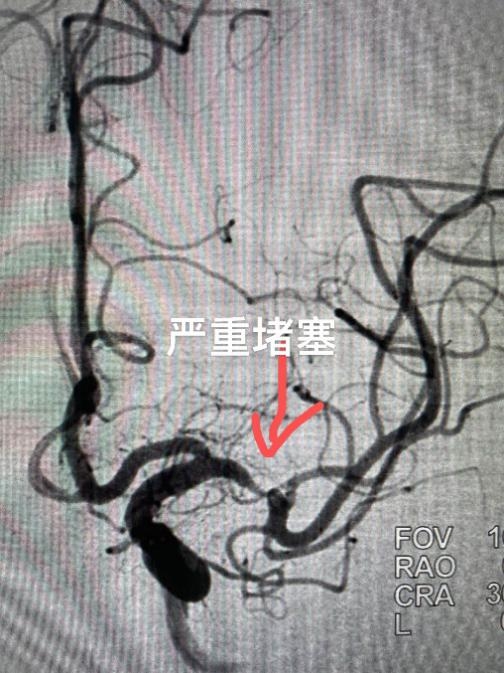

陈建一到医院,卒中中心团队马上为他安排了检查,结果提示患者左侧颅内动脉严重堵塞,并且有新发脑梗塞。由于病人是二次脑梗,而且有高血压史,平常还吸烟,这次必须得手术治疗,否则下次脑梗极可能导致严重瘫痪,这样的话家里的顶梁柱可就倒了!医生为他完善了术前评估,做好了充分的术前准备,并与家属沟通签手术同意书。

陈建接受了“微米级的微创介入手术”,医生在他的大腿股动脉处约5mm的地方开切口,穿刺股动脉,用微米级的超细导丝到达患者左侧大脑中动脉远端狭窄处,然后送入直径2.5mm的颅内动脉支架,撑开堵塞的血管,让患者血流完全恢复正常。术后第2天,患者就能下地行走,第5天就痊愈出院。